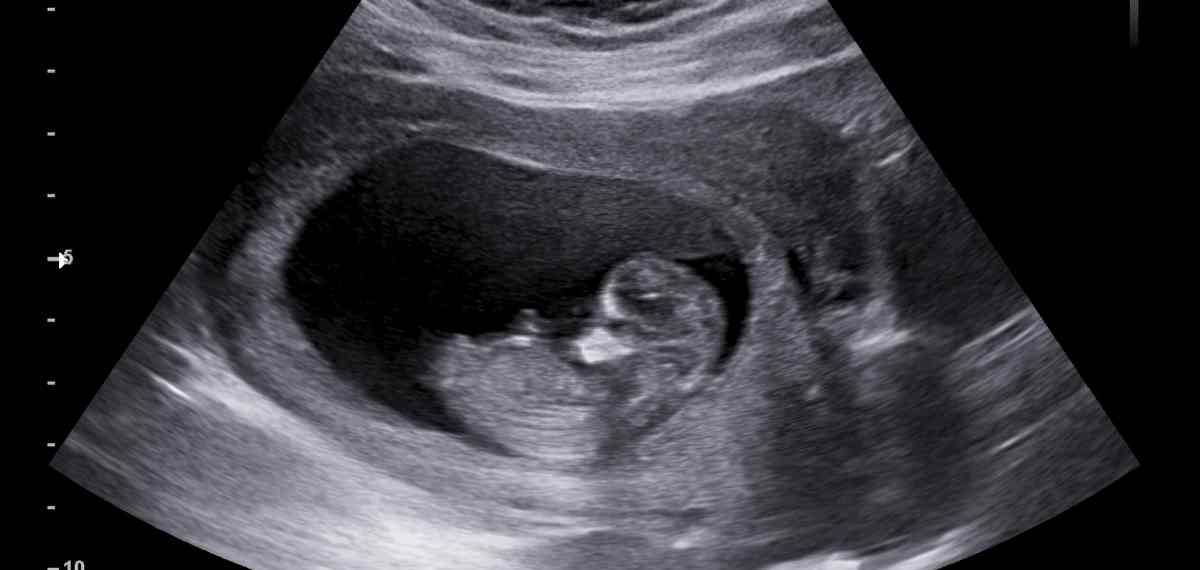

ഗർഭപാത്രത്തിനുള്ളിൽ പ്രഗ്നൻസിക്ക് (ഗർഭം) തുടക്കം കുറിക്കുന്ന 'ജനറ്റിക്ക് സ്വിച്ച്' കണ്ടെത്തിയിരിക്കുകയാണ് ഇന്ത്യൻ ശാസ്ത്രജ്ഞർ. ഈ സ്വിച്ചാണ് ഭ്രൂണം ഗർഭപാത്രത്തിലുറച്ച് വളരാൻ സഹായിക്കുന്നത്. നവംബർ 10ന് ഓൺലൈൻ റിസർച്ച് ജേർണലായ Cell Death Discoveryയിലാണ് ഇത് സംബന്ധിച്ച പഠന പ്രസിദ്ധീകരിച്ചിരിക്കുന്നത്. രണ്ടു ജീനുകൾ അടങ്ങിയ ഈ 'സ്വിച്ച്' എങ്ങനെയാണ് ഗർഭം ധരിക്കാൻ സഹായിക്കുന്നതെന്ന വ്യക്തമായ വിവരം ഈ ലേഖനത്തിലുണ്ട്.

മുംബൈ ICMR - നാഷണൽ ഇൻസ്റ്റിറ്റ്യൂട്ട് ഫോർ റിസർച്ച് ഇൻ റിപ്രൊഡക്ടീവ് ആൻഡ് ചൈൽഡ് ഹെൽത്തിലെ ഡോ. ദീപക് മോദിയാണ് ഈ ഗവേഷണത്തിന് നേതൃത്വം നൽകിയത്. HOXA10, TWIST2 എന്നീ ജീനുകളെ കുറിച്ചാണ് പഠനത്തിൽ പറയുന്നത്. ഇവ തമ്മിലുള്ള പരസ്പര സഹകരണമാണ് ഭ്രൂണം ഗർഭപാത്രത്തിലുറയ്ക്കാൻ സഹായിക്കുന്നത്. ഇവയിലൊന്ന് ഗർഭപാത്രഭിത്തികളെ അടച്ച് ഭ്രൂണത്തെ സംരക്ഷിക്കുമ്പോൾ മറ്റൊന്ന് യൂട്രൈൻ വാളിനെ മൃദുവായി തുറന്ന് ഭ്രൂണത്തെ സ്വീകരിക്കുന്നു എന്നാണ് ഗവേഷകർ പറയുന്നത്. മോളികുലാർ ബയോളജി, ജീനോമിക്സ്, കമ്പ്യൂട്ടേഷണൽ മോഡലിങ് എന്നിവയെല്ലാം അടങ്ങിയ പഠനത്തിൽ ബനാറസ് ഹിന്ദു സർവകലാശാലയിലെ ഡോ ശ്രുതി ഹൻസ്ദ, IISc ബെംഗളുരുവിൽ നിന്നുള്ള പ്രൊഫസർ മോഹിത് ജോളി, വിദ്യാർഥിയായ നാൻസി ആഷ്റേ എന്നിവരാണ് മറ്റ് സംഘാംഗങ്ങള്.

ഗർഭധാരണം നടക്കണമെങ്കിൽ ഗർഭപാത്രത്തിനുള്ളിലെ ഒരു ജീൻ സ്വിച്ച് ഓഫ് ആവുകയും മറ്റൊന്നു സ്വിച്ച് ഓണാവുകയും വേണമെന്ന് ഡോ മോദി പറയുന്നു. ഗർഭപാത്രത്തിന്റെ ഭിത്തികൾ സുരക്ഷിതമാകണമെങ്കിൽ HOXA10 സ്വിച്ച് ഓൺ ആകണം. അതേസമയം ഭ്രൂണമെത്തുമ്പോൾ ഈ ജീൻ ആ നിമിഷം തന്നെ സ്വിച്ച് ഓഫ് ആകണം, പിന്നാലെ രണ്ടാമത്ത ജീനായ TWIST2 സ്വിച്ച് ഓൺ ആയശേഷമാണ് ഭ്രൂണത്തിനായുള്ള പാത തുറന്ന് കൊടുക്കുമെന്ന് ഡോക്ടർ വിശദീകരിക്കുന്നു.

TWIST2 ഗർഭാശയ ഭിത്തിയില് ഭ്രൂണം സ്വയമേ ഉറയ്ക്കാനുള്ള പാത തുറന്നു കൊടുക്കുമ്പോള്, ഈ ഗർഭാശയ ഭിത്തിയെ സംരക്ഷിക്കുന്ന ഉത്തരവാദിത്തം HOXA10നാണ്.